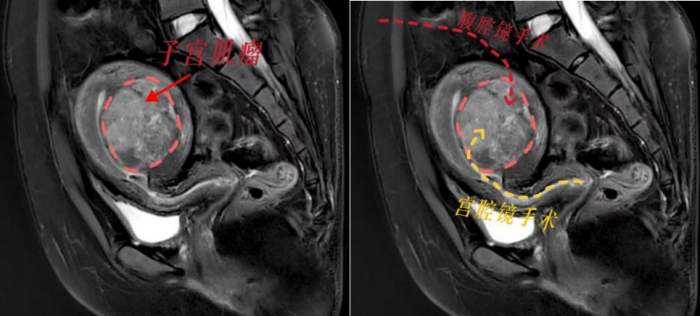

根据小丽的病情,立博体育 妇产科三区副主任魏馨分析,宫腔镜手术无需腹部切口,通过自然腔道进行,切除肌瘤无需切开子宫肌层,能最大程度保护患者生育力。但是根据子宫肌瘤诊治专家共识,像小丽这样的病例并不适合宫腔镜手术,因为手术风险极高,难以一次性切除干净,还可能引发水中毒、子宫内膜损伤等严重并发症。而如果选择腹腔镜下子宫肌瘤剥除术,就必须把子宫肌层完全切开,术后至少需要等待1年才能怀孕,且怀孕后子宫破裂的风险极大。这对于渴望成为母亲的小丽来说,无疑是沉重的打击。

面对患者强烈的生育需求,魏馨主任带领团队迎难而上,决心挑战“不可能”!经过反复研究病情和推敲手术方案,魏馨主任凭借丰富的临床经验和精湛的宫腔镜手术技巧,成功为小丽实施了高难度宫腔镜下子宫肌瘤切除手术。手术不仅一次性将肌瘤彻底切除,而且没有损伤子宫肌层和内膜,术中出血少,术后恢复快,未出现任何并发症。术后第2天,小丽便顺利出院,术后3个月即可备孕,重燃了她成为母亲的希望。